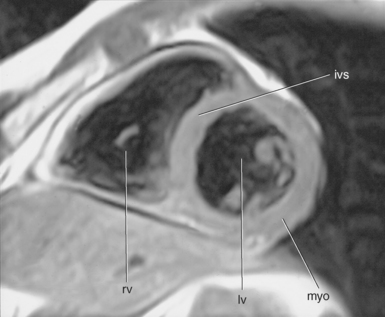

In an effort to standardize nomenclature for tomographic imaging of the heart, the Cardiac Imaging Committee of the Council on Clinical Cardiology of the American Heart Association published a statement recommending that all cardiac imaging modalities use the same nomenclature for defining tomographic imaging planes. Their recommendation stated that “all cardiac imaging modalities should define, orient, and display the heart using the long axis of the left ventricle and selected planes oriented at 90-degree angles relative to the long axis.” Their second recommendation stated, “The names for the 90-degree oriented cardiac planes used in all imaging modalities should be short axis, vertical long axis, and horizontal long axis. These correspond to the short-axis, apical two-chamber, and apical four-chamber planes traditionally used in 2D echocardiography” (Figure 6.77). We will follow these recommendations for labeling cardiac images throughout this text. In magnetic resonance (MR) imaging, each successive acquisition provides the landmarks for planning the next acquisition (view) and provides a logical method to obtain 90-degree viewing of the heart according to its intrinsic short and long axes. Several different methods can be used to obtain views of the cardiac planes during an examination, of which we provide an example of one method. To obtain the vertical long axis (VLA) view, an oblique coronal image can be positioned parallel to the interventricular septum, directly through the left atrium and ventricle (Figures 6.78 and 6.79). This plane closely approximates the right anterior oblique projection used in cineangiography and the two-chamber view used in echocardiography. The horizontal long axis (HLA) view can be obtained by angling an oblique coronal image to bisect the left ventricle, mitral valve, and left atrium (Figures 6.80 and 6.81). The HLA view demonstrates the four cardiac chambers and is comparable with the four-chamber plane used in echocardiography. The short axis (SA) view can be obtained by using the HLA image to prescribe an oblique plane through the right and left ventricles, oriented perpendicular to the interventricular septum (Figures 6.82 and 6.83).